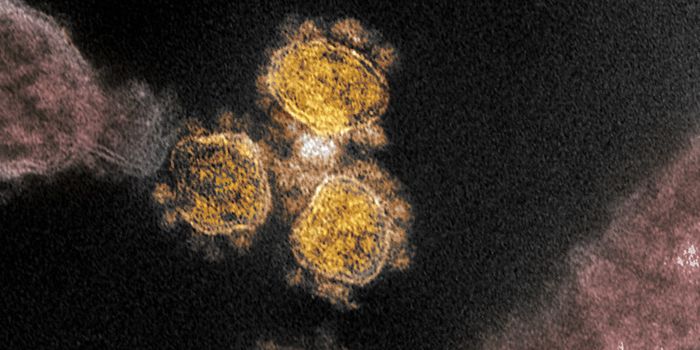

MAR 17, 2020ImmunologyStructurally, SARS-CoV-2 (the virus that causes COVID-19) are spherical shells consisting of a lipid membrane, with a co ...

MAR 19, 2020Drug Discovery & DevelopmentAs panic is spreading over the novel coronavirus, the time is ripe for both misinformation and disinformation to thrive. ...

MAY 04, 2020MicrobiologyThe COVID-19 pandemic has spread around the world and there is still no available treatment or a vaccine. Prevention rem ...

MAR 20, 2020Health & MedicineSince early statistics began to emerge from China, it seemed that COVID-19 tended to affect older people more than young ...

MAR 24, 2020Cell & Molecular BiologyACEIs and ARBs may make coronavirus infections worse, which can help explain why older adults are faring so much worse.

MAR 07, 2020Drug Discovery & DevelopmentAs COVID-19 has spread around the world, there has been a global run on surgical masks. This has led some governments, s ...

JUL 07, 2020Clinical & Molecular DXFalse-negative results are particularly problematic in containing the spread of COVID-19 — infected individ ...

MAR 25, 2020Health & MedicineCT scans from 27 patients that first contracted Cornonavirus in Wuhan, China reveal signatures in the lungs that could h ...

JUL 09, 2020ImmunologyThe number of confirmed COVID-19 cases worldwide is steadily approaching 12 million. Meanwhile, despite accelerated time ...